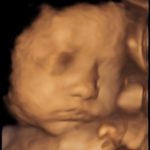

4D/5D/HD Ultrasound Gallery

Gallery